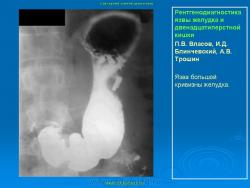

Пищеварительная система. Рентгенодиагностика язвы желудка и 12-ти перстной кишки. +

Рентгенодиагностика язвы желудка и 12-ти перстной кишки.

101.ya_.slayd45.jpg102.ya_.slayd46.jpg103.ya_.slayd16_1.jpg104.ya_.slayd17_1.jpg